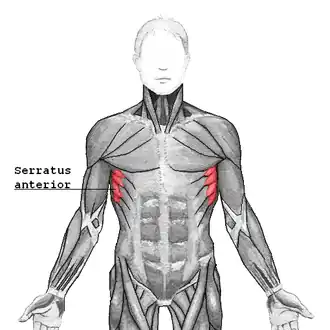

Serratus anterior muscle

| Serratus anterior | |

|---|---|

Serratus anterior, showing origin from lower ribs (origin from upper ribs obscured by pectoralis major and other superficial muscles) | |

The serratus anterior is a muscle of the chest. It originates at the side of the chest from the upper 8 or 9 ribs; it inserts along the entire length of the anterior aspect of the medial border of the scapula. It is innervated by the long thoracic nerve from the brachial plexus. The serratus anterior acts to pull the scapula forward around the thorax.